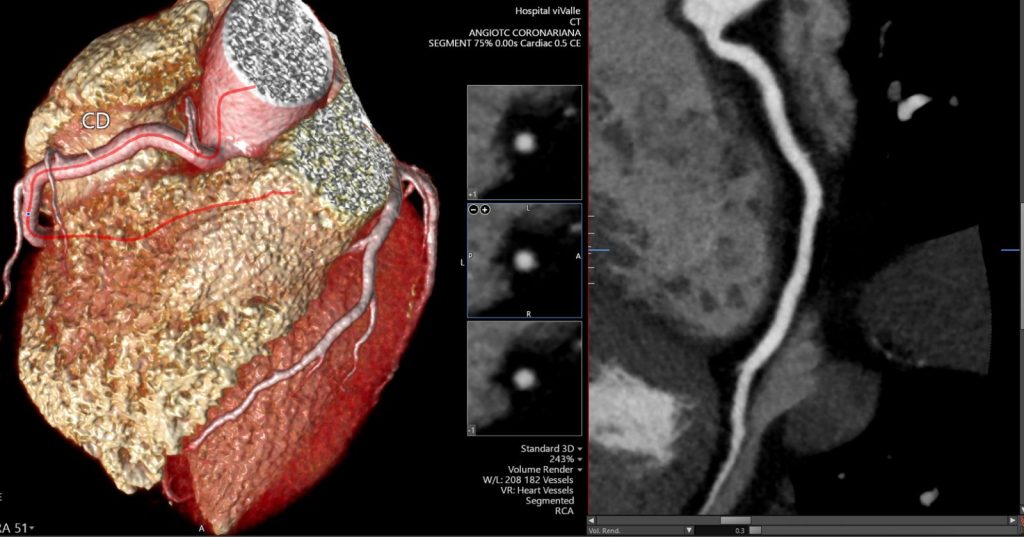

A angioTC de coronárias (CCTA) vem ganhando protagonismo na prevenção primária porque vai além do escore de cálcio: ela identifica placas não calcificadas, muitas vezes invisíveis ao CAC, e que podem representar aterosclerose ativa e risco real mesmo em pessoas classificadas como “baixo risco” pelos escores tradicionais.

Um grande estudo populacional recente (JAMA), com quase 25 mil indivíduos de 50 a 64 anos sem doença cardiovascular conhecida e seguimento de aproximadamente 8 anos, mostrou que a presença de placa não calcificada na CCTA se associou a maior risco de primeiro evento coronário e que a inclusão dessas informações anatômicas melhorou a predição de risco e a reclassificação, principalmente entre os pacientes inicialmente rotulados como baixo risco.

Na prática, isso muda o jogo: detectar precocemente placas não calcificadas permite “antecipar” o diagnóstico da doença coronária, individualizar a prevenção e orientar medidas mais assertivas — especialmente em pacientes que, pelo cálcio ou pelo risco clínico, poderiam ser falsamente tranquilizados.